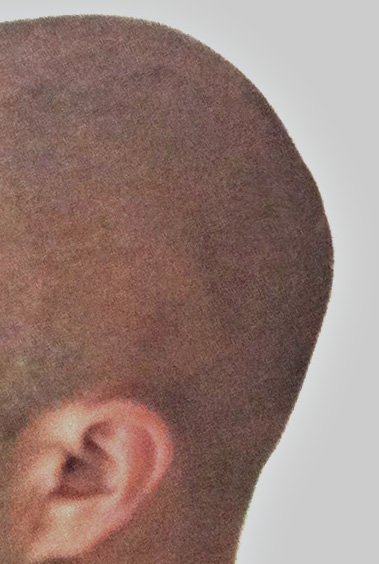

57

Scalp avulsion due to traumatic injury which left a large patch of non-hair bearing scalp.

Hair bearing scalp reconstruction using a first stage tissue expanders and second stage scalp scar removal.

Scalp avulsion due to traumatic injury which left a large patch of non-hair bearing scalp.

Hair bearing scalp reconstruction using a first stage tissue expanders and second stage scalp scar removal.